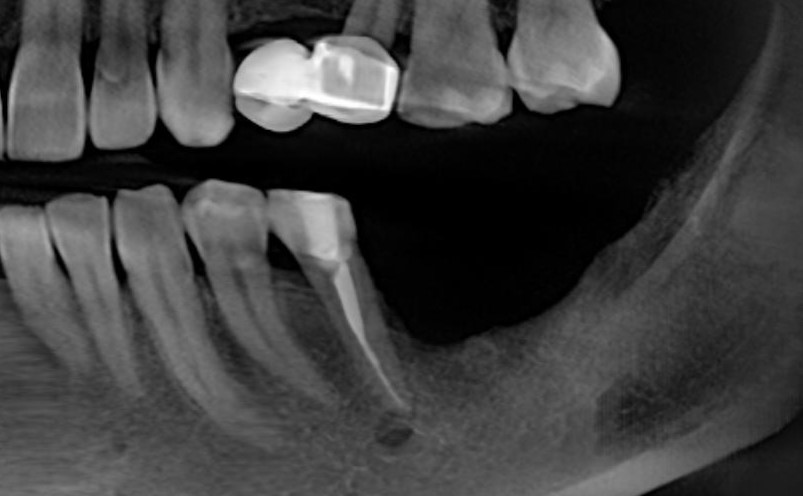

После операции мы делаем контрольные снимки. Это может быть ортопантомография:

или конусно-лучевая компьютерная томография. Как вам больше нравится.

Результат остеопластики методом остетотомии мы можем оценить уже через 4 месяца. Перед этим сделаем контрольные снимки (слева «до», справа «через 4 мес»):